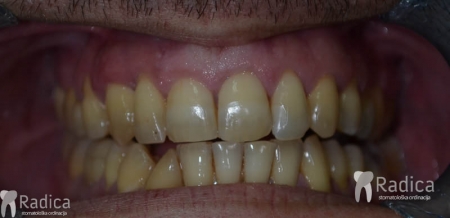

U galeriji slika su prikazani klinički slučajevi ovakvih odraslih pacijenta bilo da se radi samo o ortodontskoj terapiji ili predprotetskoj ortodonciji.

Na sljedećoj slici se mogu vidjeti početak i kraj ortodontske i protetske terapije. Protetske radove radio je dr. Goran Radica.

Na sljedećoj slici mogu se vidjeti početak i kraj ortodontske terapije. Pacijentica je upućena od svog stomatologa nakon što nije bila zadovoljna izgledom osmjeha i odnosom zuba i gingive u privremenom protetskom radu. Napravljena je ortodontska terapija samo u gornjoj čeljusti a nakon toga novi privremeni protetski rad.